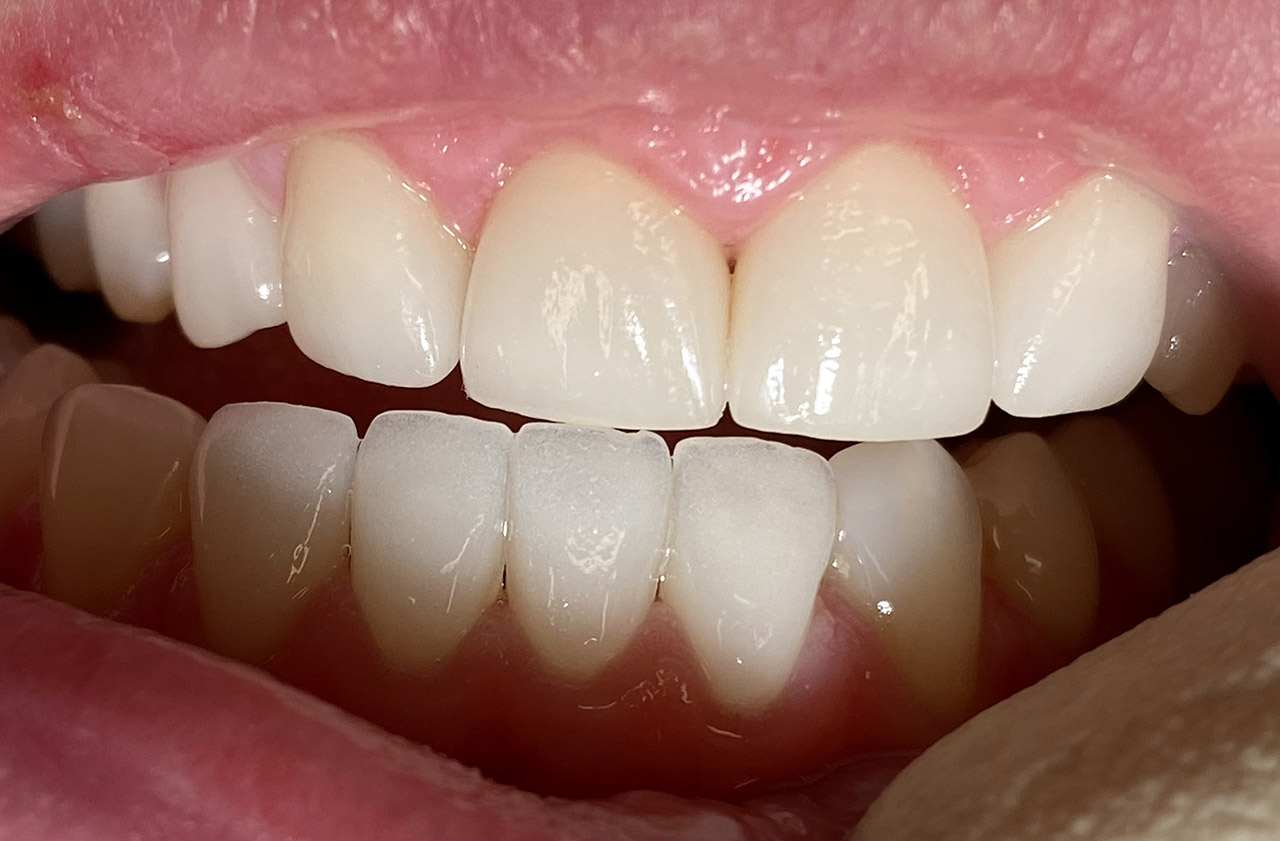

Traumatologie und Endodontie:

Nach Unfall/Sturz mittlerer Schneidezahn auf Gingivaniveau abgebrochen, Pulpa weit eröffnet, beide Nachbarzähne ebenfalls frakturiert.

Erstversorgung: Pulpektomie der Kronenpulpa, MTA, provisorischer Verschluß mit rosa Glasionomerfüllung.

Wiederaufbau der Nachbarzähne mit mitgebrachten (plus 1 Stein) Zahnstücken mit Kunststoff ergänzt und adhäsiv verklebt.

2. Schritt nach Aushärtung von MTA: Entfernung der Kronenpulpa im Bruchstück zur Vermeidung von Verfärbung, Füllung mit Kunststoff.

Adhäsives zementieren des abgebrochenen Zahnstücks.